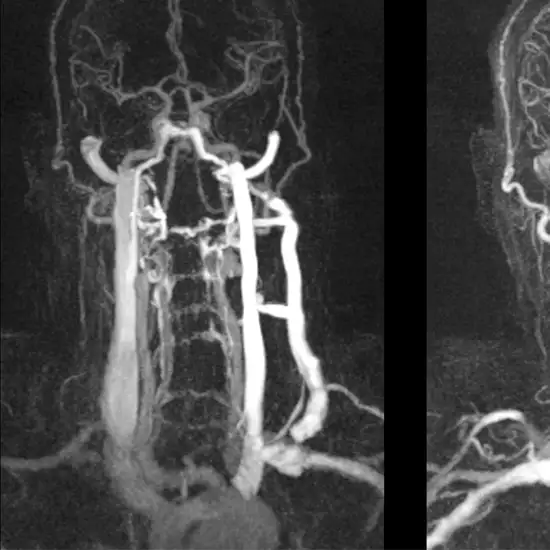

CTA (Computed Tomography Angiography) Neck Vessel is an imaging procedure that uses a rotating x-ray beam to take detailed images of blood vessels present in the neck region. This scan is used to diagnose the weekend section of arteries for the flow of blood. The scan is useful in diagnosis of the blood vessel abnormalities like blockages, vessel tears, injuries or weakened vessels.

CT angiography neck vessel test scan is the imaging tool to create detailed images of the blood vessels of the neck to check for any abnormality. The full form of CT is computed tomography in CT angiography neck.